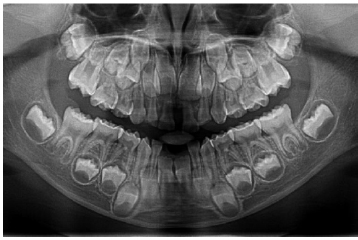

A 3-year-old female patient presented to a dental practice in Lesvos, Greece, in 2015, following the exfoliation of her lower primary central incisors shortly after their eruption. According to her parents, this was initially believed to be self-induced, prompting them to seek dental consultation. Clinical examination revealed intact roots on the exfoliated teeth, no gingival inflammation or bleeding, and no mobility of the other teeth. These findings were consistent with cementum deficiency rather than inflammatory periodontal disease. Anthropometric measurements were within the normal range for age and sex, and family history was negative for premature loss or metabolic disorders. Upper and lower occlusal radiographs were obtained to assess the status of her dentition (Fig. 1). Based on the clinical findings and history, hypophosphatasia (HPP) was suspected, and the child was referred to the hospital for diagnostic workup. Metabolic testing revealed markedly elevated plasma pyridoxal-5′-phosphate (PLP) levels, consistent with tissue-nonspecific alkaline phosphatase deficiency.

Upper and lower occlusal radiographs at age 3, following exfoliation of the mandibular primary central incisors, demonstrating a normal eruption pattern and absence of pathological changes.